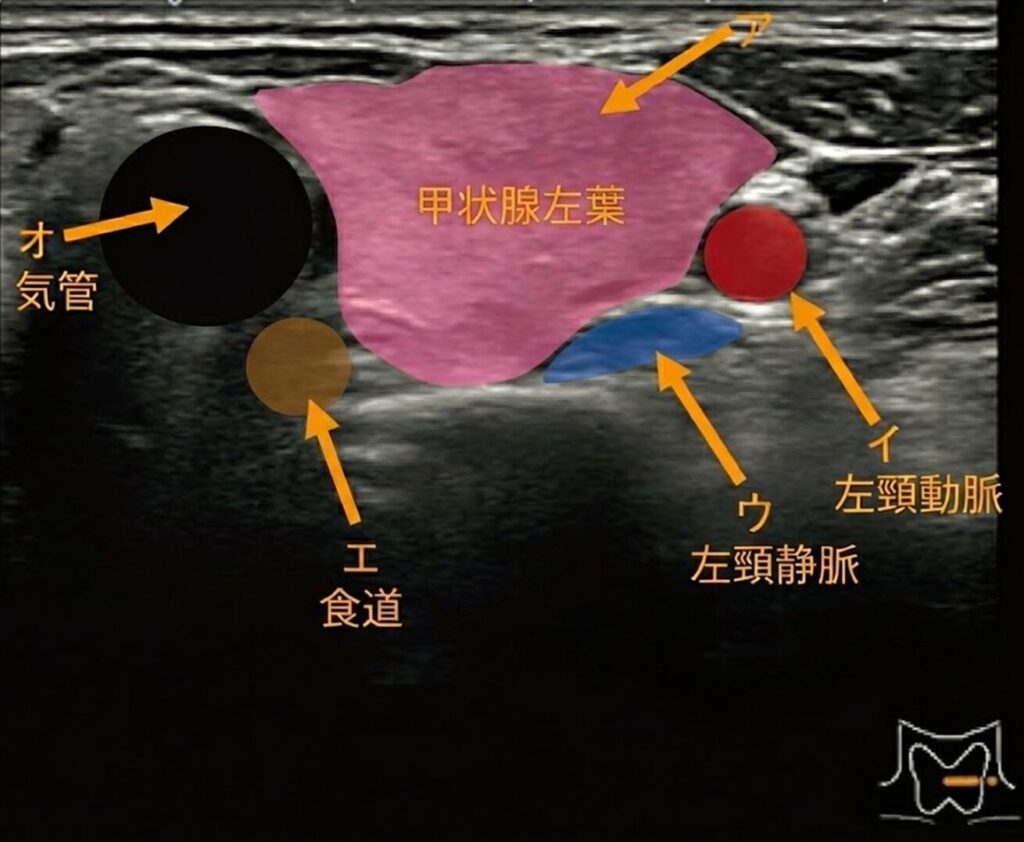

頸部超音波像を示す。 総頸動脈はどれか。

- ア

- イ

- ウ

- エ

- オ

2.イ

- ア(甲状腺左葉)

- 画面中央に広がる、少し白っぽい(中等度エコー)実質臓器です。これがメインの甲状腺です。

- イ(総頸動脈)

- 甲状腺の外側に位置する、真ん丸で真っ黒な管。

- ウ(内頸静脈)

- 動脈のさらに後方にある、少し潰れたような形の黒い管。

- エ(食道)

- 甲状腺の背側(後ろ)に隠れている、層構造(何層かのリング状)を持った管。

- オ(気管)

- 画面中央(甲状腺の峡部の下)にある、中に空気を含んだ構造。空気は超音波を跳ね返すので、表面が白く光り、後ろは真っ暗(シャドウ)になります。

今回の画像では、「イ」はきれいな円形を保っています。これは内圧が高い証拠、つまり動脈です。 一方、「ウ」は少し平べったくなっていますね。これは静脈の特徴です。